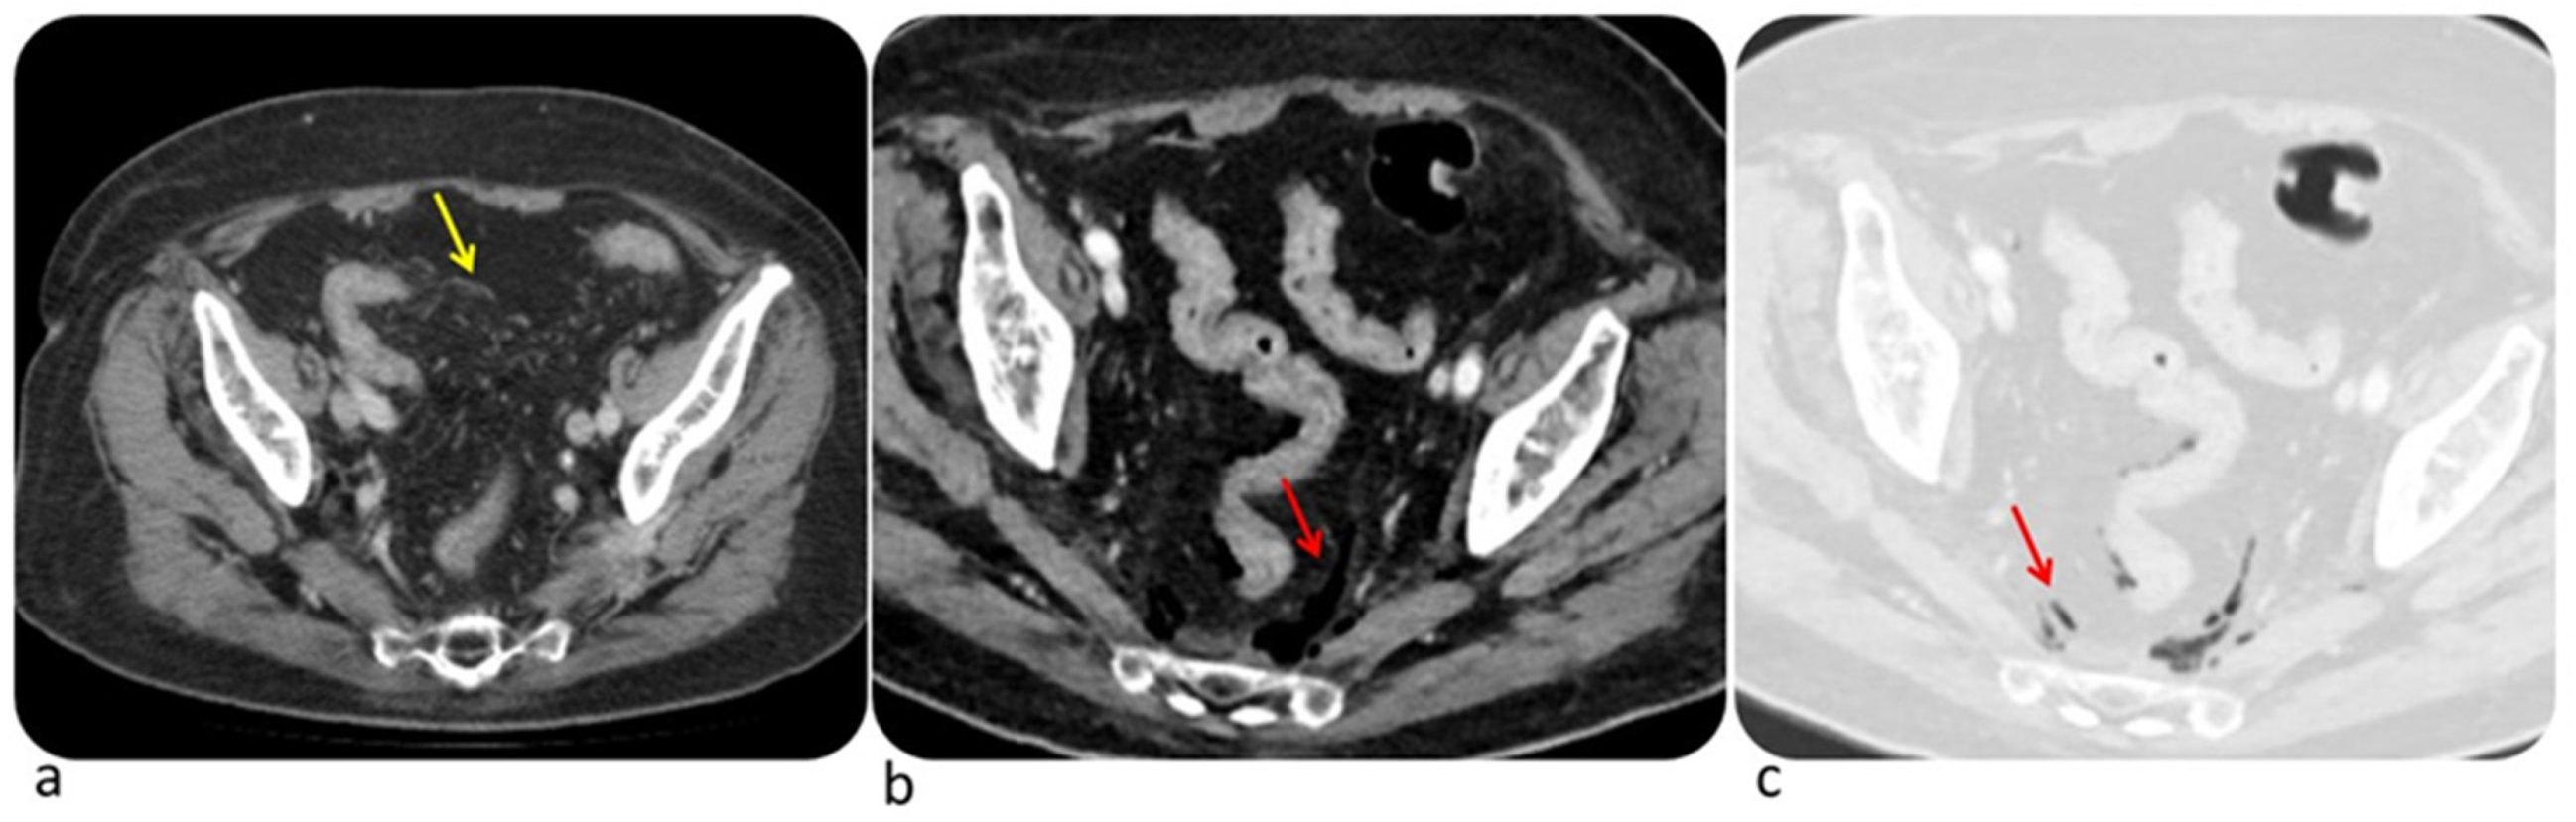

6.1. Colon

| Diffuse Colitis | Segmental Colitis |